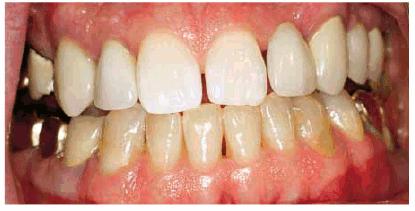

INTRINSIC STAINS

Much of the etiology of internal stains has been discussed in the first volume

of this textbook. Typically, bleaching with 10% carbamide peroxide in a

custom-fitted tray easily treats discolorations due to aging, smoking, or

chromogenic foods, and beverages (Figures 16-16A 16-16B 16-17A, and 16-17B). Although these types of stains

generally require only 2 to 6 weeks of bleaching treatment, some are more

stubborn. Nicotine staining of long-term duration may require as long as 3

months of nightly treatment (Figures 16-18A, and 16-18B).48 Tetracycline

staining may take anywhere from 2 to 12 months of nightly treatment.49

Figure 16-16A: Some teeth darken over time from chromagenic foods. Some patients' teeth are just naturally yellow.

Figure 16-16B: Whitening of the maxillary teeth using 10% carbamide peroxide in a custom tray results in a more pleasing smile. This patient is now interested in closing the spaces.

Figure 16-17A: Some teeth darken through natural aging.

Figure 16-17B: Whitening of the maxillary teeth using 10% carbamide peroxide in a custom tray produces a normal progression of color from gingival to incisal edge but offers a more pleasing, younger look to the patient.